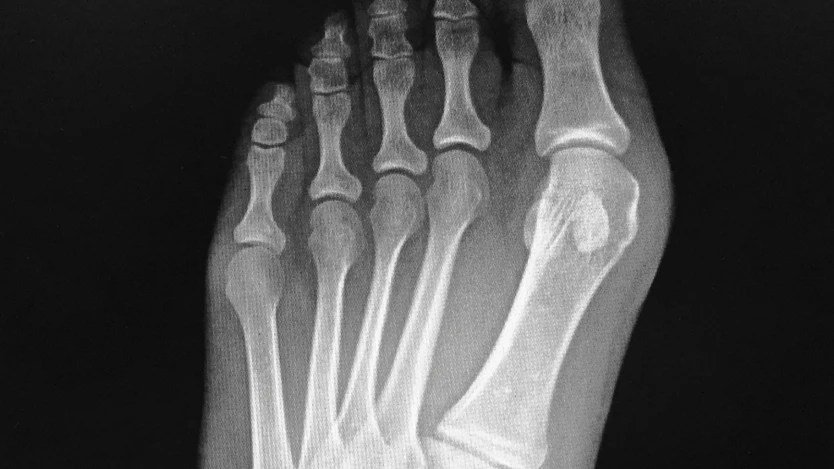

Your initial follow-up appointment usually falls within this timeframe, around day 10 to 14 post-surgery. During this visit, your surgeon will remove any sutures and change your bandages. This is also when your doctor will likely perform an initial X-ray to assess how the bone is healing and confirm the stability of the surgical correction.

At approximately six weeks, you'll have another follow-up appointment, which will include new X-rays. These images are critical for your surgeon to assess the progress of bone healing and confirm that sufficient bone fusion has occurred. This confirmation is a key green light for advancing your recovery.